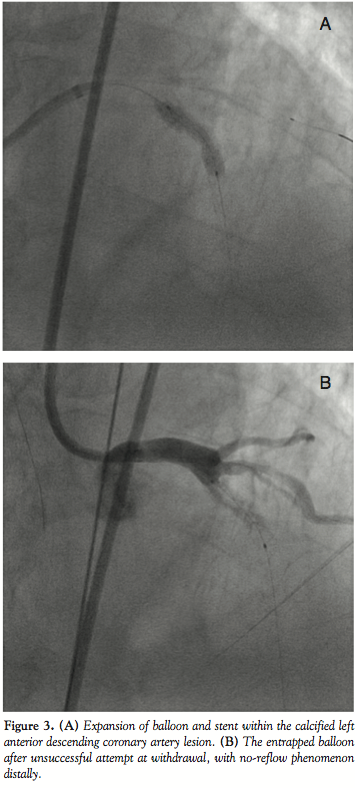

On day 3, the patient was brought back to the cath lab for staged PCI. An 8 French (Fr) Amplatz™ Left (AL) 2.0 guide (Boston Scientific, Natick, Massachusetts) was selected for increased support, and a Whisper™ wire (Abbott Vascular, Abbott Park, Illinois) was advanced easily through the lesion. Due to the lesion proximity to a large ramus intermedius bifurcation, a BMW™ wire (Abbott Vascular) was placed in the ramus for protection from potential plaque shift. A 3.0 x 20 mm Voyager™ NC noncompliant balloon (Abbott Vascular) was used for predilation, inflated at 14 atm for 30 seconds, to apparent full expansion. A Cypher sirolimus-eluting stent (on Bx Velocity™ platform [Cordis Corporation, Miami Lakes, Florida) was requested, but was not stocked in the 3.5 x 23 mm size that was required. Thus, a 4.0 x 24 mm Taxus paclitaxel-eluting stent (on Liberte™ platform [Boston Scientfic]) was chosen, deployed at 16 atm for 30 seconds. Postdeployment cineangiography appeared to demonstrate full expansion of the stent within the target stenosis (Figure 3A). However, when attempts were then made to withdraw the balloon into the guide, it would not disengage from the stent scaffolding.

Subsequent views with the balloon in place revealed no-reflow distal to the stent (Figure 3B). A number of techniques were applied in attempts to free the balloon (see discussion below), but were proven unsuccessful. Ultimately, after all other percutaneous options to disengage the balloon were exhausted, the surgical backup team was alerted, and the patient was accepted for an emergent CABG. The patient was transferred directly to the surgical suite, where he underwent LAD bypass. Coronary arteriotomy at the level of the balloon and stent was performed, the balloon catheter and stent were removed, and a vein patch was applied. The stent and balloon were quite deformed (Figure 4). The postoperative course was uneventful, and the patient was discharged on postop day 13.